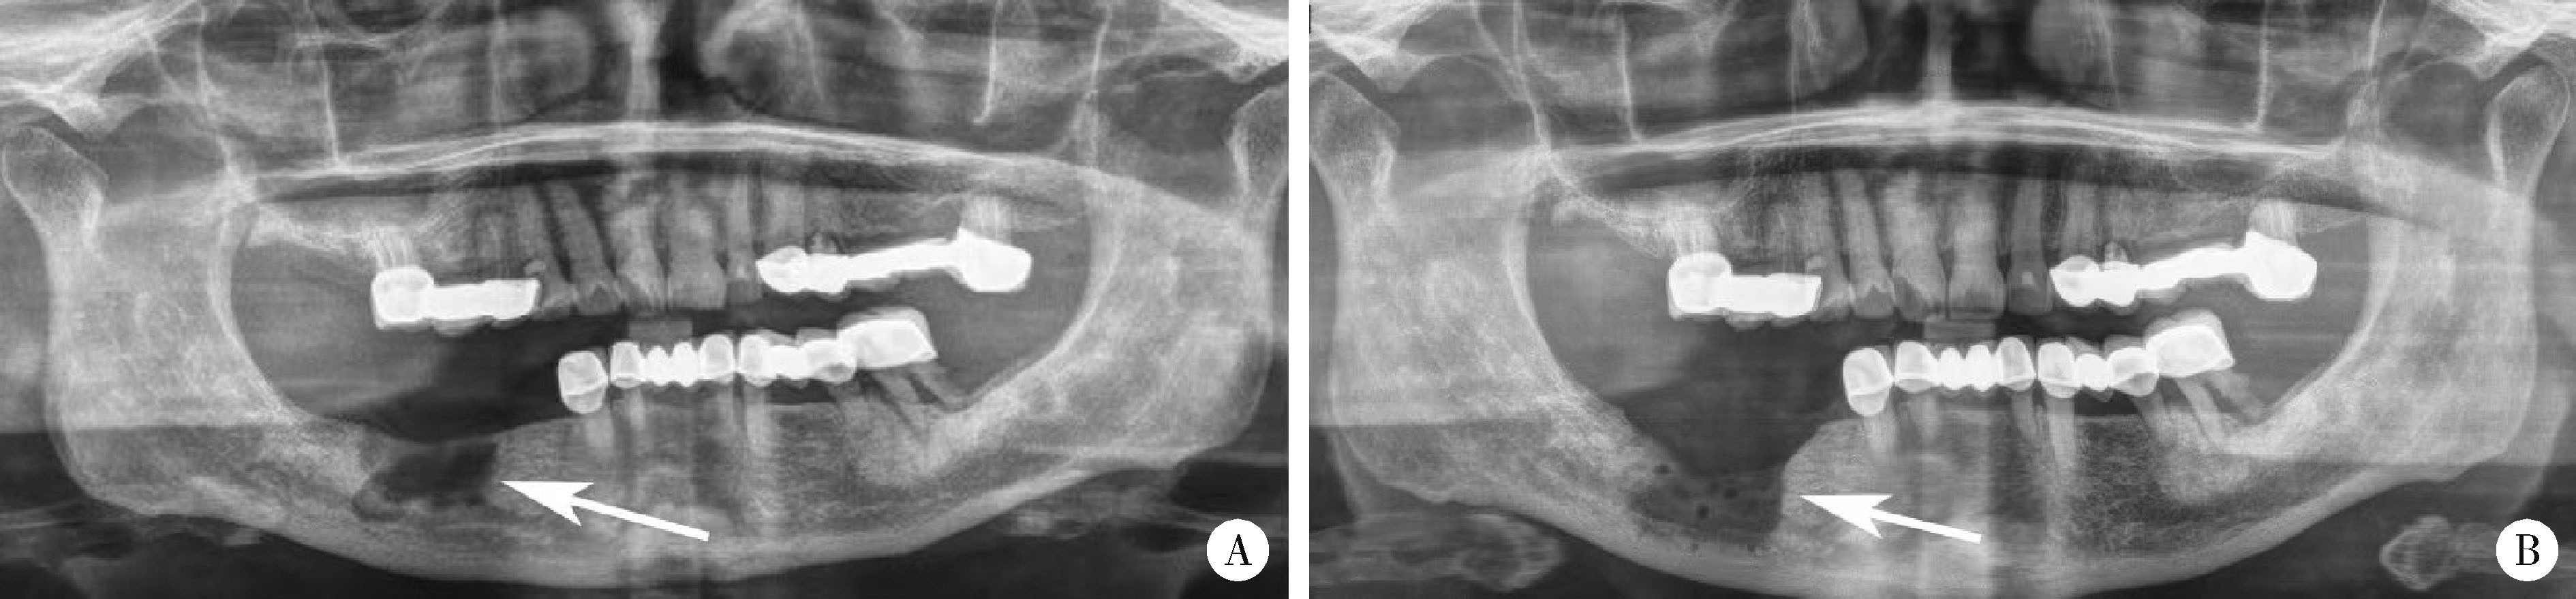

Figure 1

Preoperative and postoperative X-ray findings of mandibular osteonecrosis A, the preoperative X-ray showed right mandibular osteonecrosis bone destruction (arrow); B, the X-ray findings of the jaw after operation (arrow)."